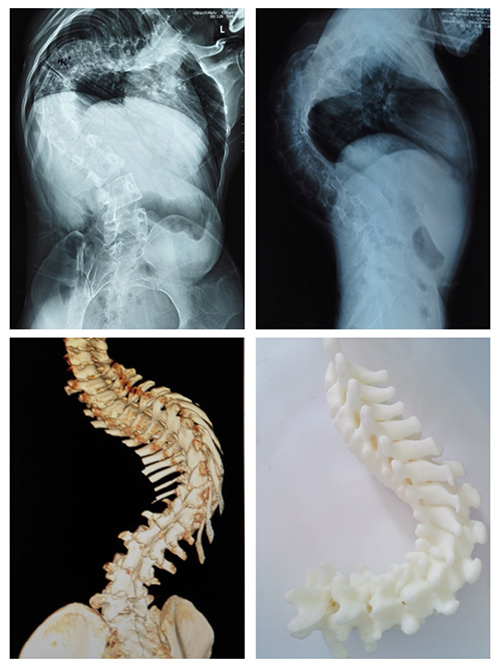

案例二:患者李某,男,16岁,文山州广南县某中学学生。2007年(6岁时)发育时发现双侧肩背部不等高,当地县医院诊断为“脊柱侧弯”。同样也是由于治疗技术所限,10年来,他脊柱侧弯逐渐加重,跑动时出现运动耐量下降。相比陶某,他平时行走尚未出现喘息。李某于8月初到色漫网 就诊,收入骨科。

骨科医生经过对李某进行脊柱X线片,三维CT及MRI等项检查,发现侧弯Cob角达135°,后凸Cob角达80°,并发现患者胸椎有半椎体畸形。

此次色漫网 骨科收治的两位患者,病史较长,病情严重,如果贸然进行矫形手术,可能术中脊髓神经牵拉过度出现下肢瘫痪;或者可能因脊柱小关节僵硬,导致矫形效果不满意。因此经色漫网 骨科专家及省内其他专家会诊,两例患者术前均采用骨牵引办法,分别实施颅骨牵引及双侧股骨髁上骨牵引,牵引时间为4周,以松解小关节及神经根。牵引期间患者可坐起进食。

术后患者外观均有明显改善。

李某侧弯Cob减小50°,后凸Cob角减小30°。